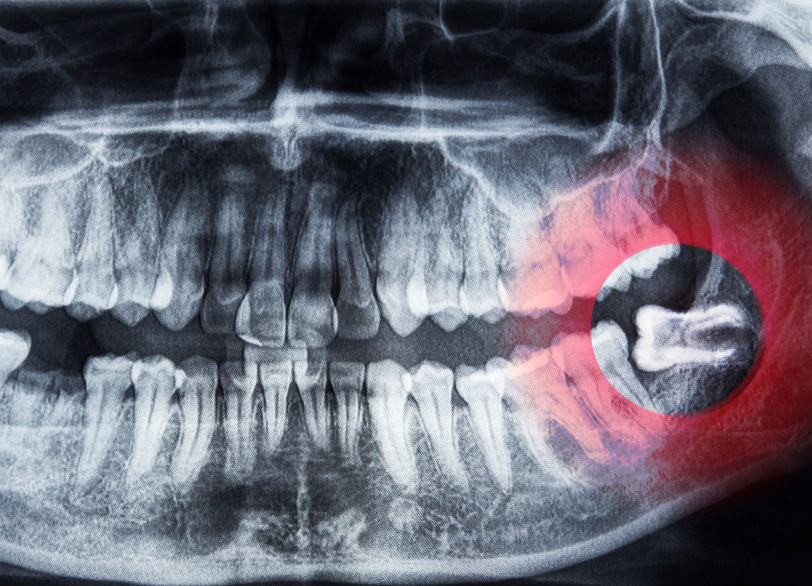

CTを用いた精密な「3次元診断」

安全な抜歯を行うためには、事前の正確な診断が不可欠です。

親知らずの根の先には、下顎管(かがくかん)という太い神経と血管が通っています。

万が一、抜歯の際にこの神経を傷つけてしまうと、唇や舌に麻痺が残るリスクがあります。従来のレントゲン(平面)では、神経と歯の位置関係を正確に把握することは困難でした。

当院では、歯科用CT(3次元断層撮影装置)を完備しており、神経と歯の距離や根の形、骨の厚みを立体的に確認することができます。

「神経に接しているか」「どの方向に力をかければ安全に抜けるか」を事前にシミュレーションすることで、偶発的な事故を防ぎ安全で確実な手術を実現します。